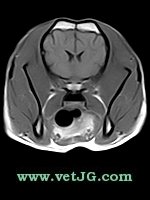

RESONANCIA MAGNÉTICA

AXIAL